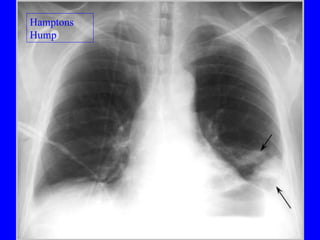

Diagnosis CXR Usually reveals a non specific abnormality.  14% normal Classic abnormalities include: Westermark’s Sign - focal oligemia Hampton’s Hump - wedge shaped density Enlarged Right Descending Pulmonary Artery (Palla’s sign)

PE Hamptons   Hump

Diagnosis CXR Usuallyreveals a non specific abnormality. 14% normal Classic abnormalities include: Westermark’s Sign - focal oligemia Hampton’s Hump - wedge shaped density Enlarged Right Descending Pulmonary Artery (Palla’s sign)